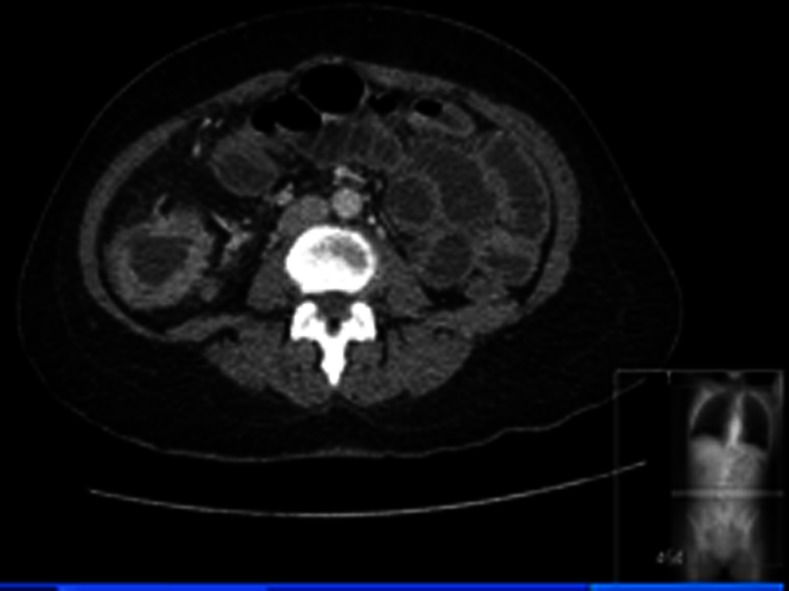

CT with contrast revealed a 10 cm long segment stricture of the hepatic flexure of transverse colon (figure 1) and a second annular wall thickening of the caecum (figure 2). There was also moderate dilation involving the proximal colon and few subhepatic lymph nodes, appearances suggesting synchronous colonic carcinoma. CT chest was normal.

Figure 2.

CT abdomen showing an annular caecal lesion.